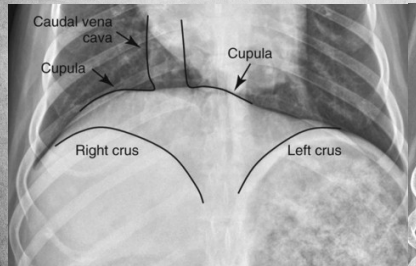

What view is this?

DV

Q

VD